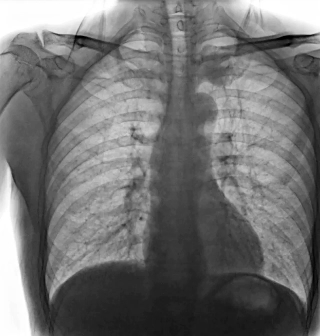

靜態(tài)DR受限于二維成像,在拍攝隱匿性病灶時,由于組織重疊病灶難辨,耗費時間更長且易漏診、誤診。而動態(tài)DR則具備實時動態(tài)成像功能,可通過實時連續(xù)成像,對于重疊部位病灶或者易被遮擋的病灶進行多角度動態(tài)觀察,快速實現動靜態(tài)轉換點片。

因此,動態(tài)DR在精準診斷方面具有顯著優(yōu)勢。首先,有效減少誤診漏診,如胃腸道造影中,可實時觀察鋇劑的流動和充盈過程,精準發(fā)現病灶部位,避免靜態(tài)DR攝片時機不當的問題。其次,提升復雜檢查能力,如食管吞咽功能評估、四肢關節(jié)動態(tài)活動度評估等,動態(tài)DR都能提供關鍵性的診斷依據。同時,還可以優(yōu)化流程效率,醫(yī)生在擺位時能通過動態(tài)影像快速找到最佳投照角度,減少重復拍片,降低患者輻射劑量。